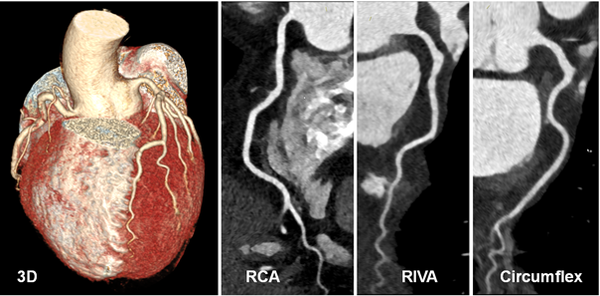

- Kardio-CT mit Koronar-CT-Angiographie: Die hochauflösende Herz-CT (Kardio-CT) mit Darstellung der Herzkranzgefäße (Koronar-CT-Angiographie) ermöglicht detaillierte Einblicke in Herzstrukturen und hat sich insbesondere für die Beurteilung der Herzkranzgefäße als hervorragende nicht-invasive Alternative zur Herzkatheteruntersuchung etabliert. Bei gleichzeitig deutlich reduzierter Strahlenbelastung kann dank modernster CT-Technologie nicht nur eine 3D-Darstellung des kompletten Gefäßbaums der Herzkranzgefäße angefertigt werden, sondern es können auch winzige Verkalkungen oder weiche Plaques in den Gefäßen visualisiert und quantifiziert werden. Auf diese Weise leistet diese CT-Untersuchung einen wertvollen Beitrag zur Abschätzung des Herzinfarktrisikos der untersuchten Patientinnen und Patienten.

Bei dieser 80-jährigen Patientin fiel bei der Herzkatheteruntersuchung ein ungewöhnlicher Verlauf der Koronararterien auf. Die CT-Koronarangiographie lässt die genauen anatomischen Verhältnisse sehr schön erkennen: Es liegt ein gemeinsamer Ursprung sämtlicher Koronararterien im Bereich des rechten Koronarostiums vor (*) mit Verlauf des linken Hauptstamms zwischen der Lungenarterie und der Aorta auf die eigentlich linke Herzseite. Häufig sind dies auch Zufallsbefunde, die jedoch gerade bei jüngeren Patienten eine therapeutische Konsequenz haben können.